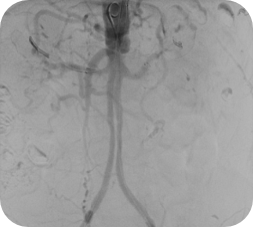

Guider